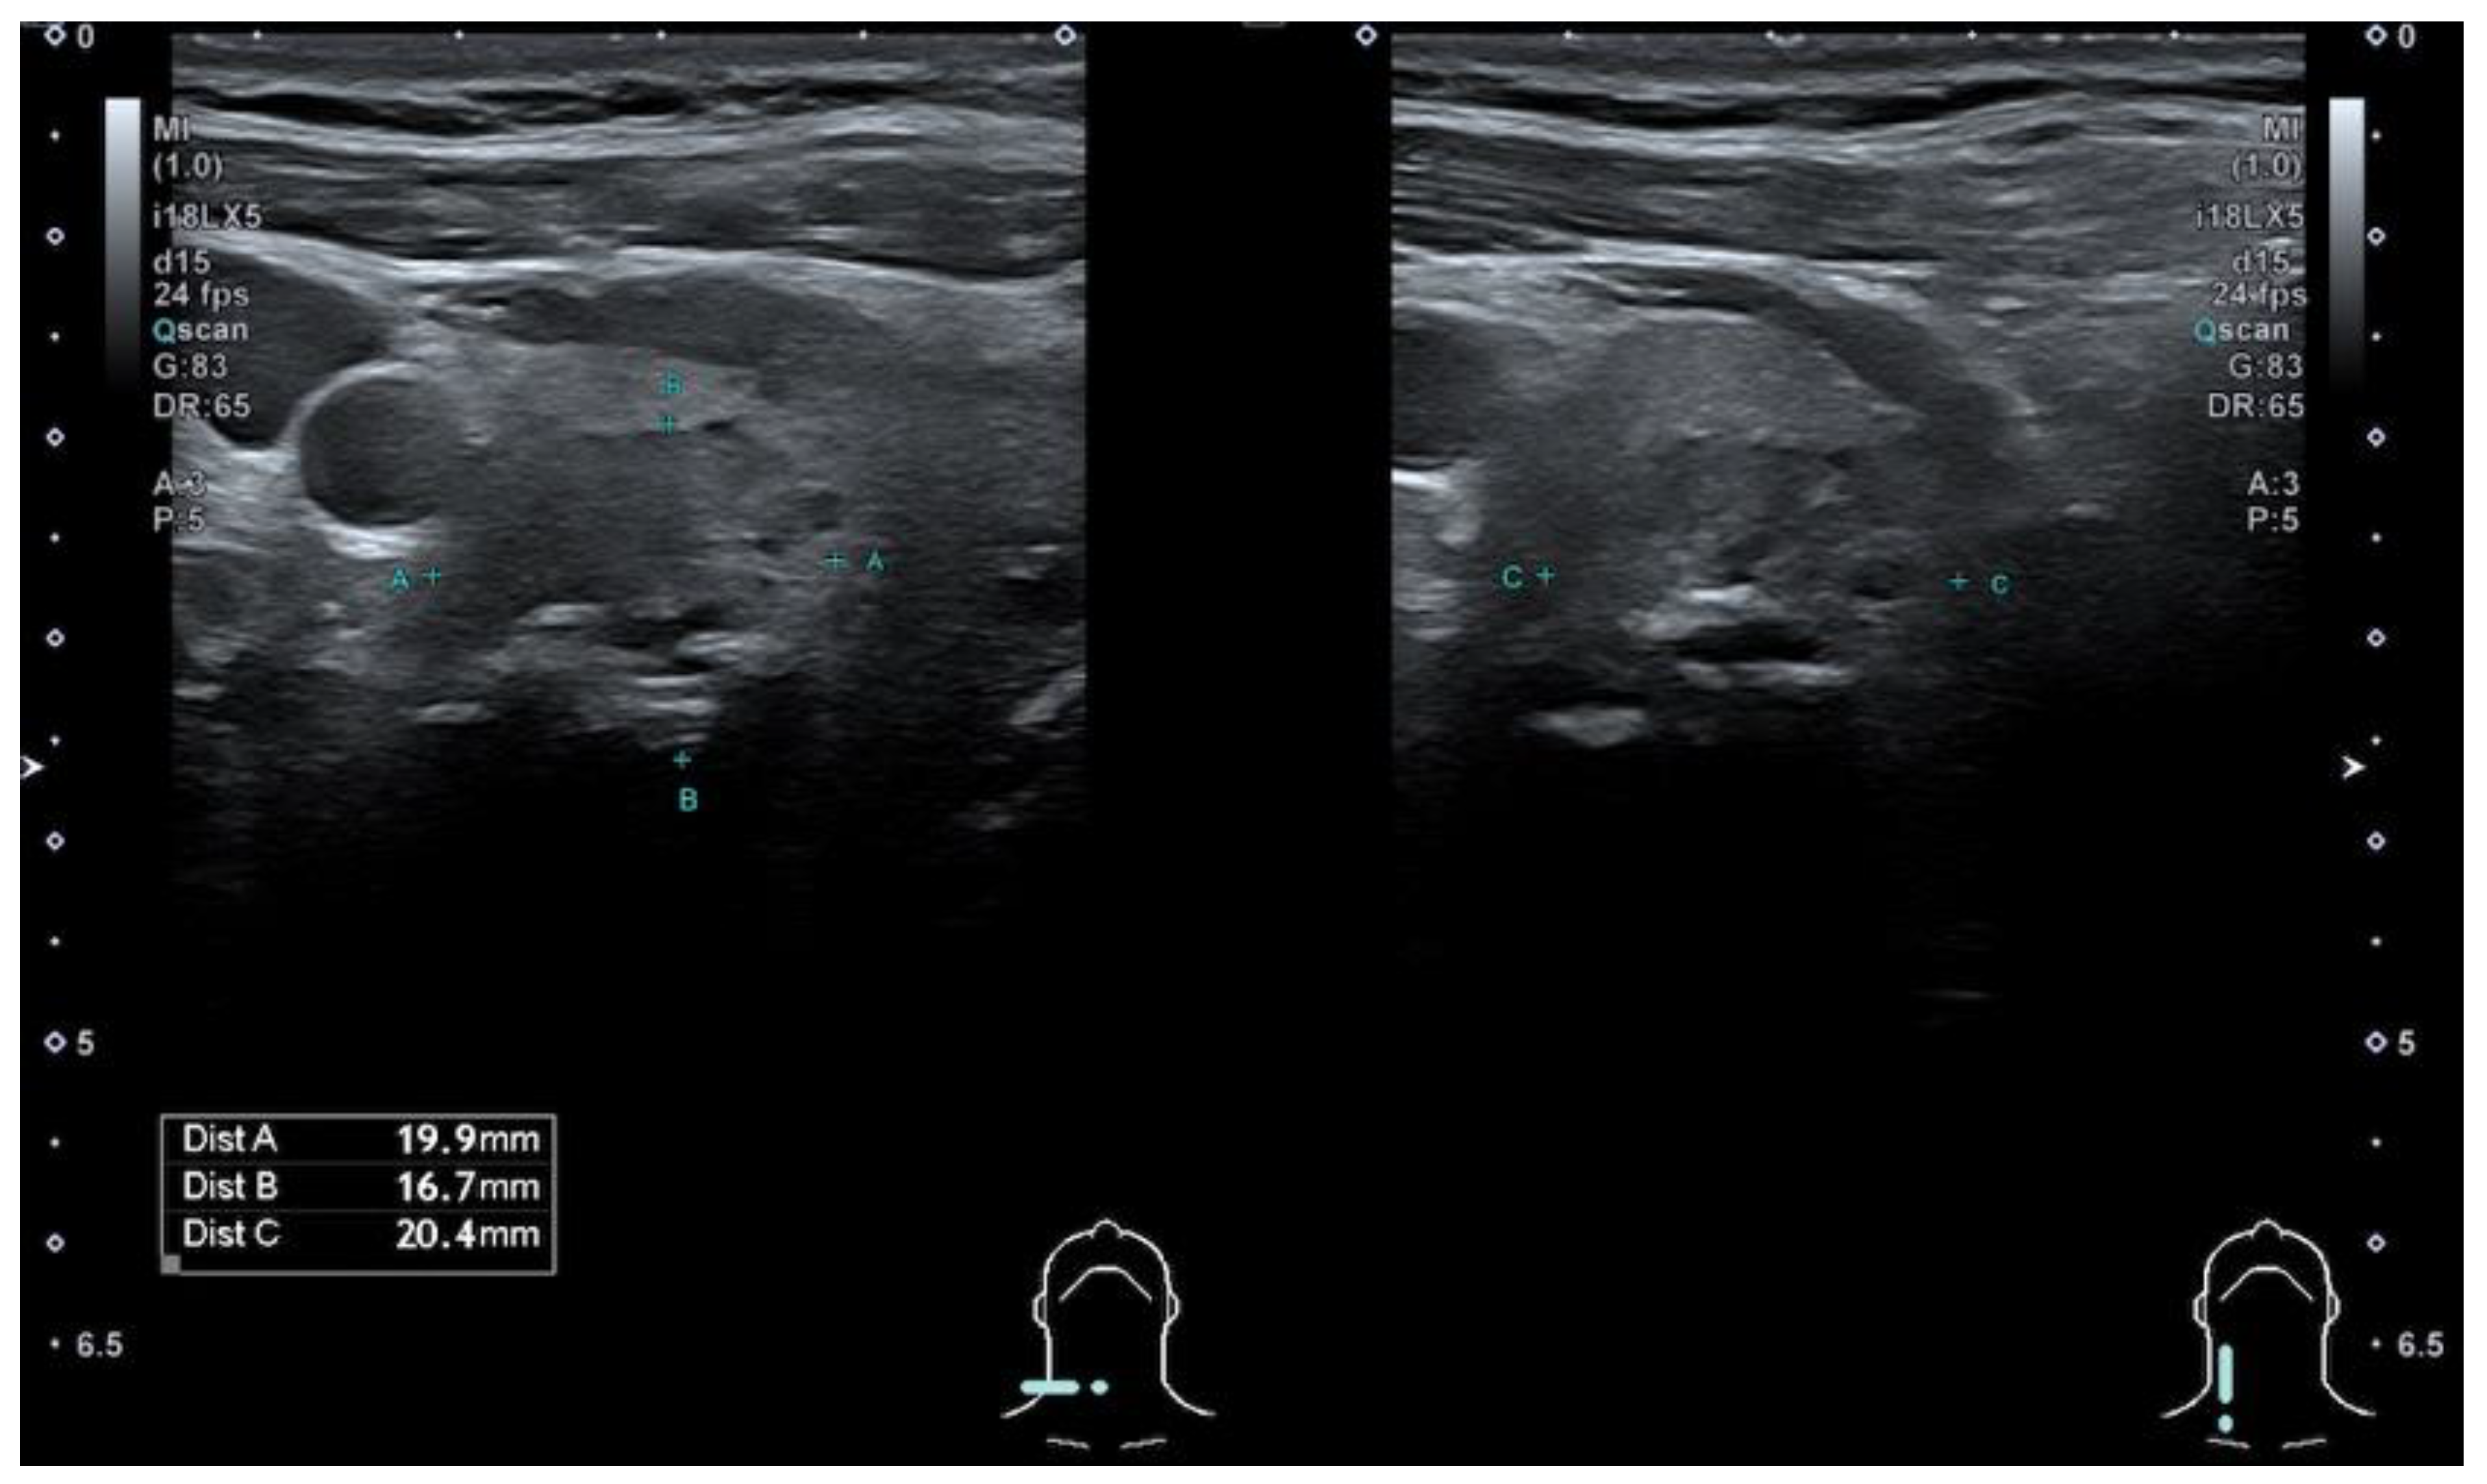

The modified Kwak et al. TIRADS system [21] that is used in Latvia (L-TIRADS) is based on the count of suspicious signs of ultrasound, which include marked hypoechogenicity, microcalcifications, taller than wide shape, irregular or microlobulated/ spiculated margins and metastatic lymph nodes. TIRADS 1—normal thyroid tissue without nodules. TIRADS 2 includes simple cysts, spongiform nodules, hyperechogenic nodules in patients with chronic autoimmune thyroiditis; multinodular hyperplastic goiter without separate bounded nodules; isolated macrocalcifications. TIRADS 3 includes partly cystic nodules; solid nodules with isoechogenic, hyperechogenic, moderately hypoechogenic structure, without any independent sign of malignancy (Figure 1 and Figure 2). TIRADS 4A—one ultrasonographic sign of malignancy, 4B—two ultrasonographic signs of malignancy, 4C—three ultrasonographic signs of malignancy, and 5—four and more ultrasonographic signs of malignancy.

Figure 1. Hypoechogenic, ovoid, smooth, non-homogeneous solid thyroid nodule with cystic component and macrocalcification in its structure—categorized as TIRADS 3 by modified Kwak et al. (L-TIRADS), TIRADS 4 by European and Korean TIRADS, TIRADS 5 (5 points) by ACR TIRADS systems. FNA results—Bethesda 2 (benign).

Figure 2. Hypoechogenic nodule, ovoid shape, smooth margins, non-homogeneous solid thyroid nodule with cystic component and macrocalcification in its structure—TIRADS 3 by modified Kwak et al. (L-TIRADS), TIRADS 4 by European and Korean TIRADS, TIRADS 5 by ACR TIRADS systems. FNA biopsy results—Bethesda 2.